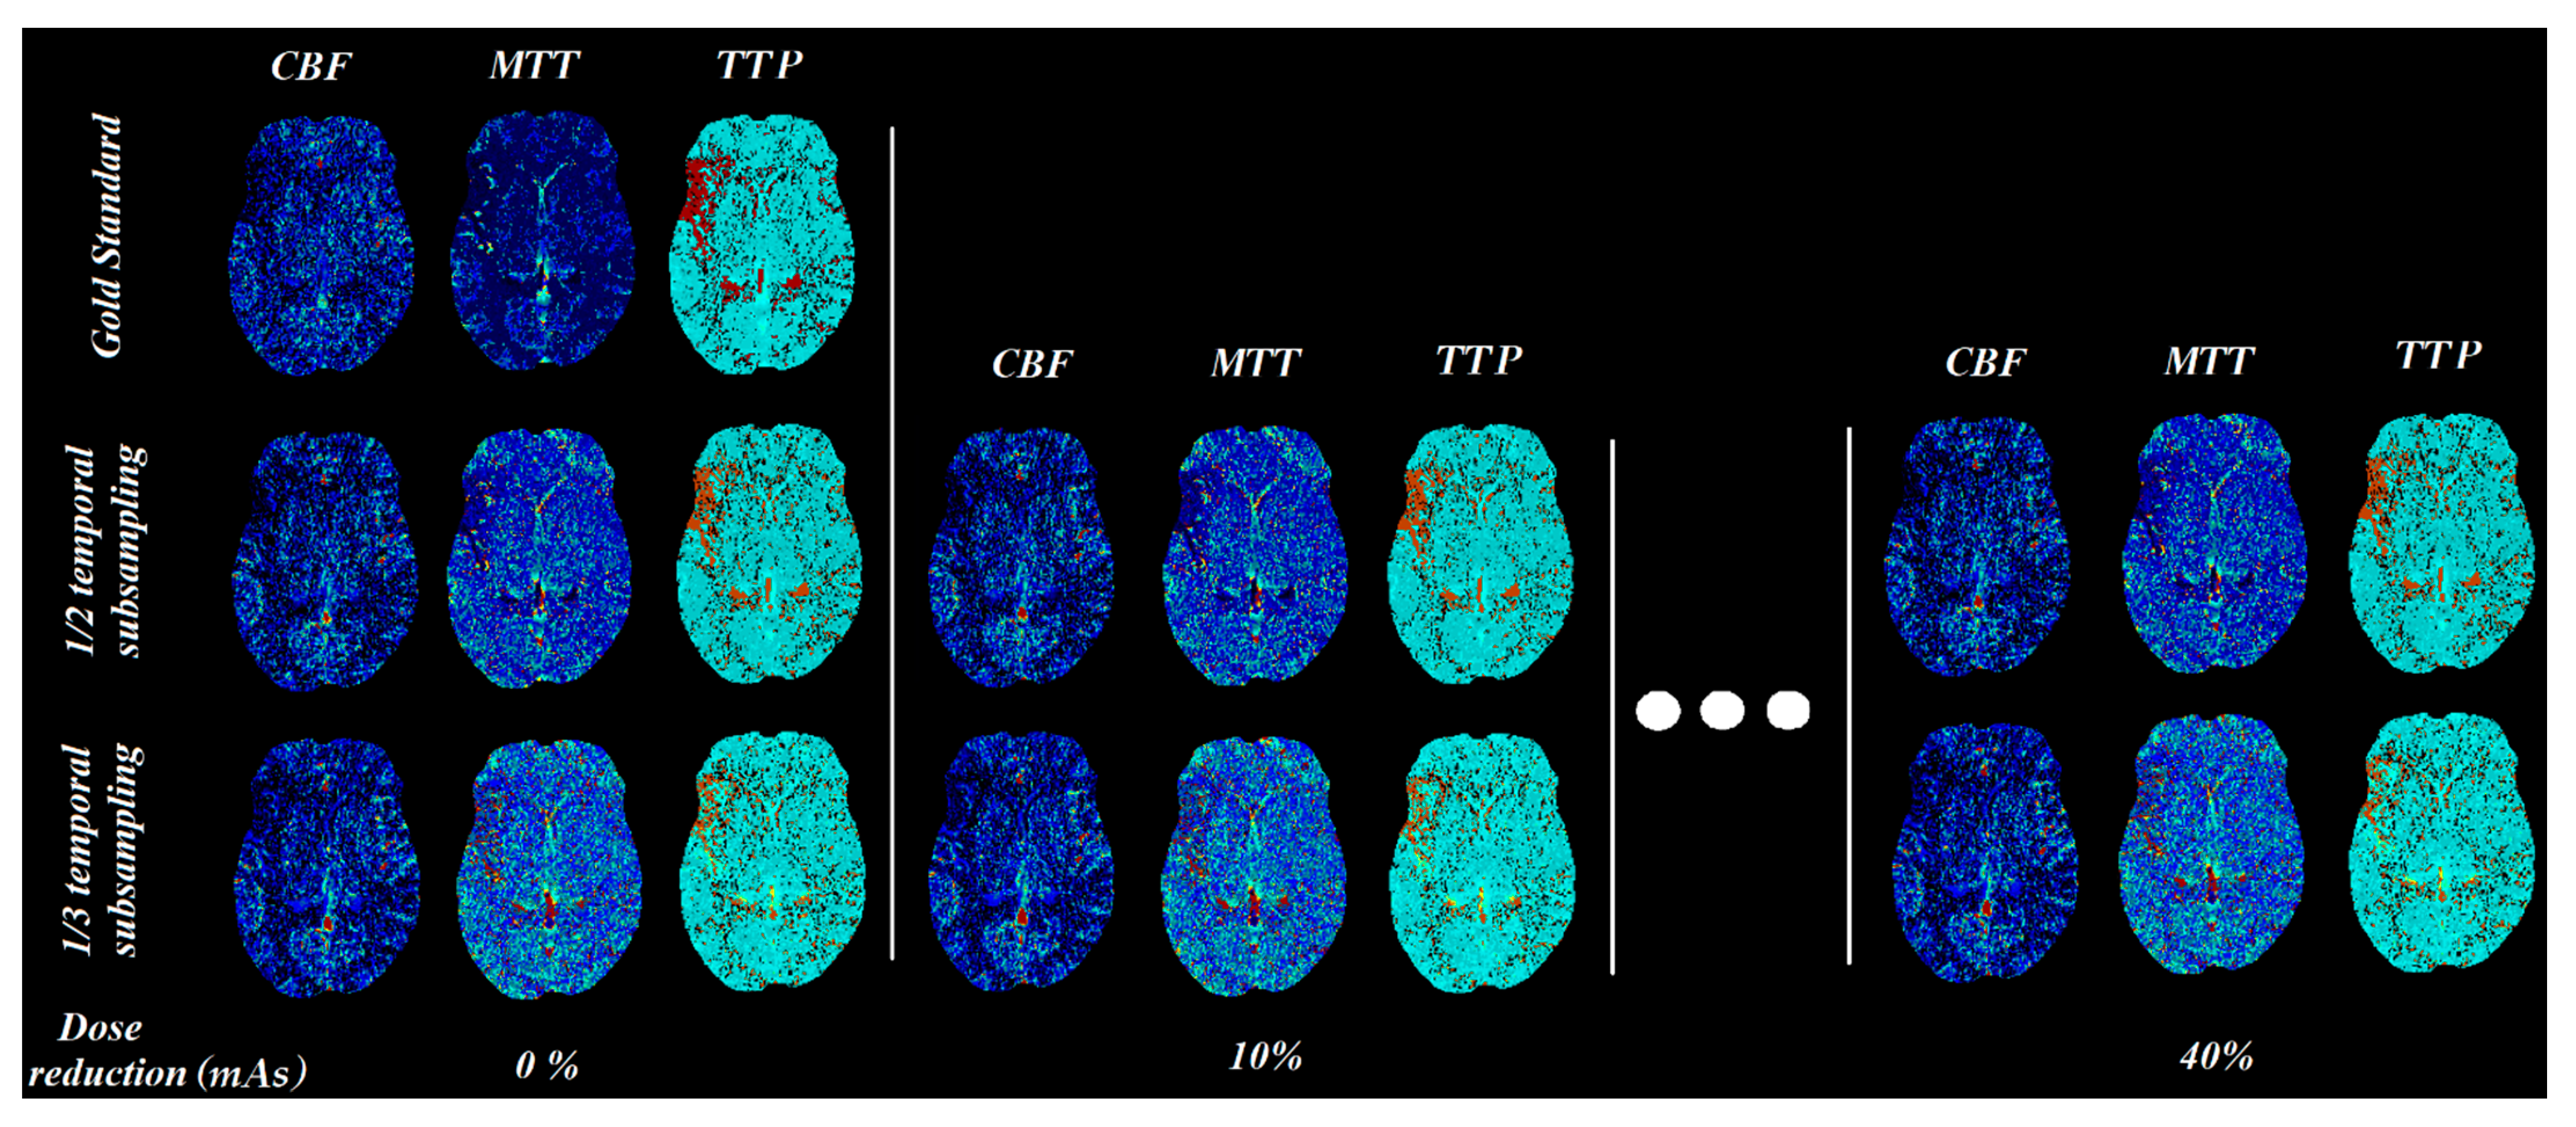

| 1/2 Temporal Resolution | ||||||

|---|---|---|---|---|---|---|

| Perfusion Parameters | Original Protocol | 0% mAs Reduction | 10% mAs Reduction | 20% mAs Reduction | 30% mAs Reduction | 40% mAs Reduction |

| CBV (mL mL−1) | 0.361 | 0.739 | 0.756 | 0.759 | 0.772 | 0.779 |

| CBF (mL mL−1 s−1) | 0.199 | 0.182 | 0.187 | 0.19 | 0.194 | 0.196 |

| MTT (s) | 3.138 | 5.351 | 5.332 | 5.278 | 5.254 | 5.209 |

| MSI (HU/s) | 0.912 | 1.751 | 1.743 | 1.751 | 1.766 | 1.794 |

| TTP (s) | 20.346 | 17.796 | 17.872 | 17.831 | 17.814 | 17.664 |

| 1/3 Temporal Resolution | ||||||

| CBV (mL mL−1) | 0.361 | 1.22 | 1.323 | 1.336 | 1.379 | 1.431 |

| CBF (mL mL−1 s−1) | 0.199 | 0.199 | 0.204 | 0.205 | 0.209 | 0.211 |

| MTT (s) | 3.138 | 5.413 | 5.632 | 5.618 | 5.763 | 5.886 |

| MSI (HU/s) | 0.912 | 2.299 | 2.281 | 2.305 | 2.322 | 2.354 |

| TTP (s) | 20.346 | 18.908 | 18.979 | 18.94 | 18.92 | 18.796 |